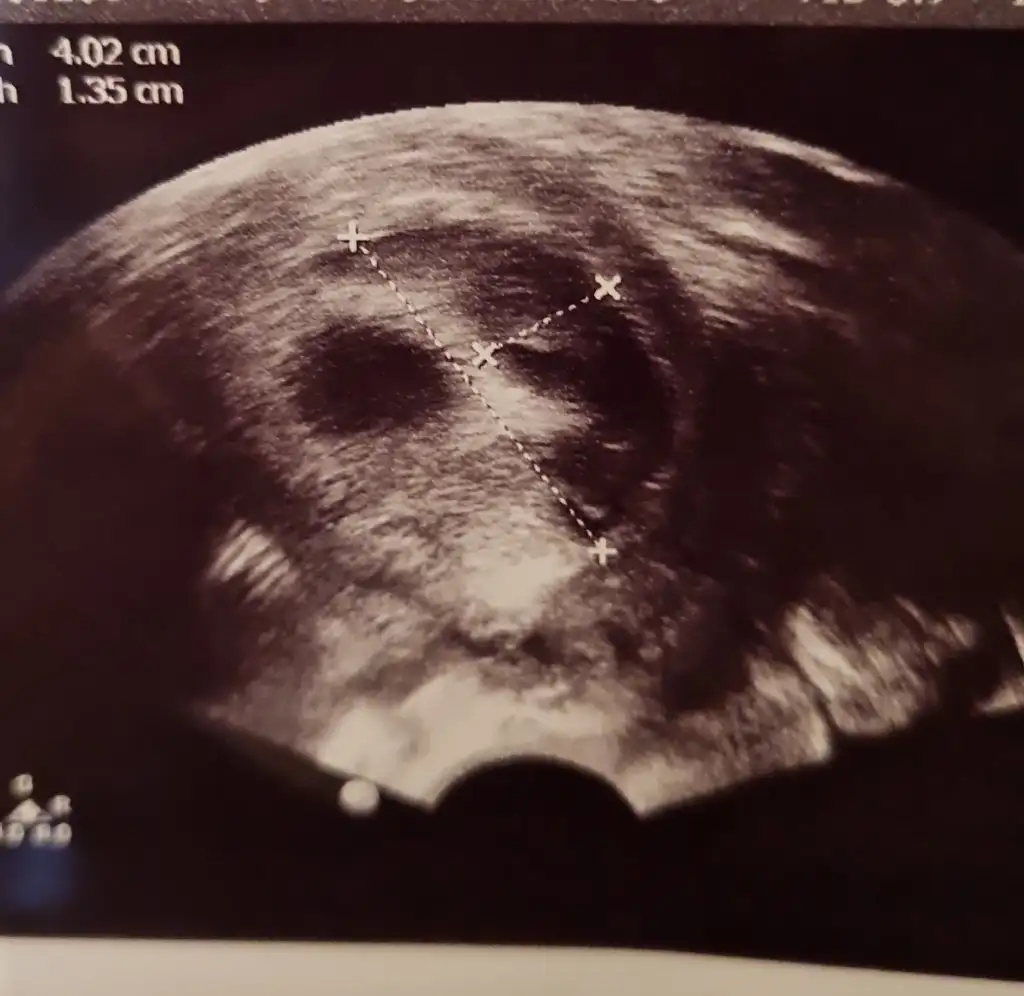

arkadaslar bebegimi ilk gormeye gittigimizde 5+4 tu yolk kesesini gorduk ve gayet iyiydi hersey smdi 7+2 de hem bebisimi hemde kalp atisini gormeye gitcektik 7+1 birgun once gece ani bi kanamayla acile gittik kanamam adet gibi yogundu ve asiri buyuk ciger gibi kan pihtilari dustu ertesi gun doktorumla randovumuz vardi zaten gittik bebisin kalp atisini duyduk bebekte iyiydi kesede zarar gormemisti ama kanama alanima acildeki doktorda kendi doktorumda cok buyuk dedi 4.2 cmye 1.35 cm cikti benim bebegim tup bebek gunde 3 kere yumurta toplamadan beri fitil seklinde progestan 200 kullaniyodum smdi + olarak progestan dex igne verdi gunde 1 adet doktorumun dedigi dinlenmem agir is yapmamam bebek eger saglikliyla bisey olmicagini soyledi hatta kanin akmasi hastalari korkutsada onu memnun ediyomus basinc olusturmuyomus boylelikle icerde bebek buyudukce rahimde daha fazla yer kaplamaya basladikca kanama dururmus bu boyutlarda bi kanama yasayan var mi yada boyle bi kanama yasayip sonrasi ne oldu kanama alaninin gorselini ekliyorum tarali alan

benim dun kontrolum vardi kanama alanimiz daha cok buyumus alanimiz onceden 4 x 1.3 cm di simdi 5 x 4 kusur dedi ama bebis gayet iyi benim doktorum kanin akmasini istiyoki birikmesin iceride basinc yapmasin diye birde akarsa daha hizli bosalir vucudun emmesini beklersek daha gec biter diyo o yuzden bence sizde korkmayin sizin cmleriniz nasil ben eski ve gunceli koyuyim tekrar ama bu kontrolde karindan baktigi icin sol saga dondu aynalama oldu yani siz tukenmezle cizili olan resmi kan alani sagda dusunun lutfen